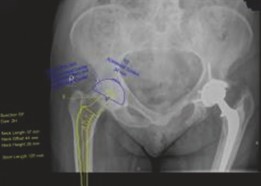

Digital templating is the gold standard for preoperative planning. It allows for:

* Component Sizing: Accurate estimation of femoral stem and acetabular cup sizes.

* Offset Restoration: Planning to restore the natural femoral and global hip offset, which is crucial for abductor muscle tension and hip stability.

* Leg Length Assessment: Precise planning to correct or prevent leg length discrepancy.

* Femoral Canal Morphology: Detailed assessment of the femoral canal (Dorr classification, cortical thickness) to guide cemented stem selection (e.g., straight, bowed, collared, collarless). The stem should provide adequate fill in the diaphysis and a robust cement mantle.

* Acetabular Bone Stock: Evaluation of acetabular osteophytes, bone defects, and the integrity of the anterior and posterior columns.

* Trialing: Digital manipulation of template components to simulate intraoperative sizing and placement.

Pre-operative templating showing planned component sizes and positions for a THA.